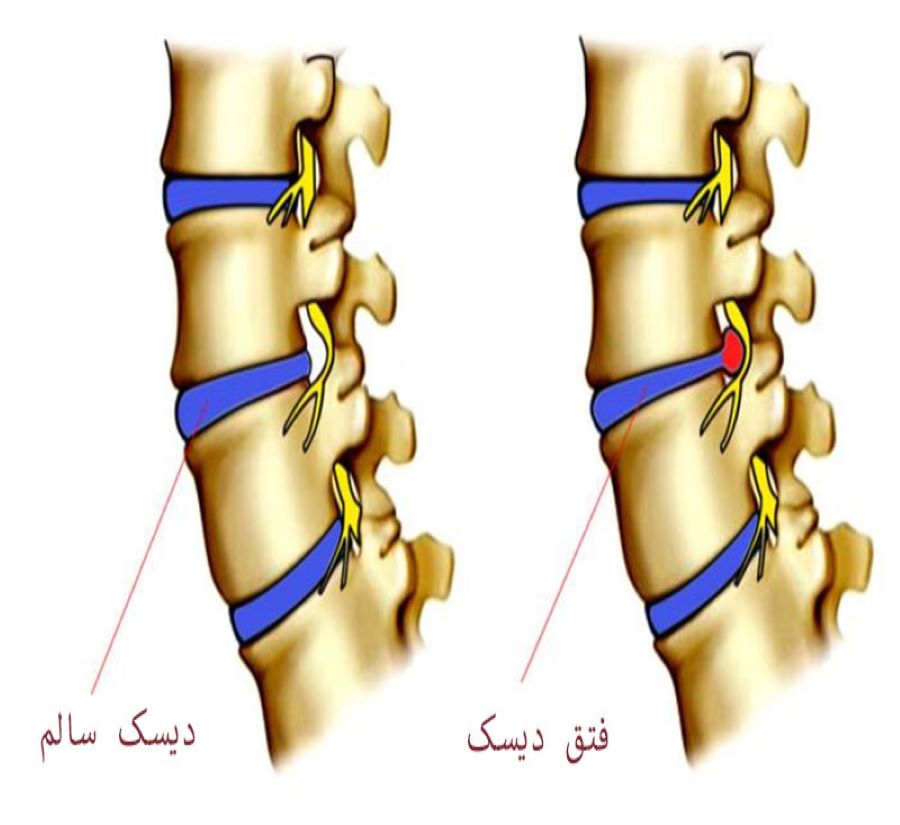

بیماری دیسک کمر

دیسک کمر دلیل شایع بسیاری از دردهای حاد، مزمن و دردهای عود کننده ی کمر و پا می باشد. معمولا بیشترین آسیب ها در دیسکهای L4-L5 یا L5-S1 ایجاد می شود ولی گاهی ممکن است در دیسک های بالاتر کمری نیز مشکل وجود داشته باشد. درد ممکن است در پائین کمر، باسن، لگن و پاها احساس شود.

ریسک فاکتورها برای ایجاد دیسک کمر:

چاقی و اضافه وزن

سنین 20 تا 70 سالگی

سابقه ی فامیلی (ژنتیک)

عطسه، سرفه، فشار و حرکات ناگهانی